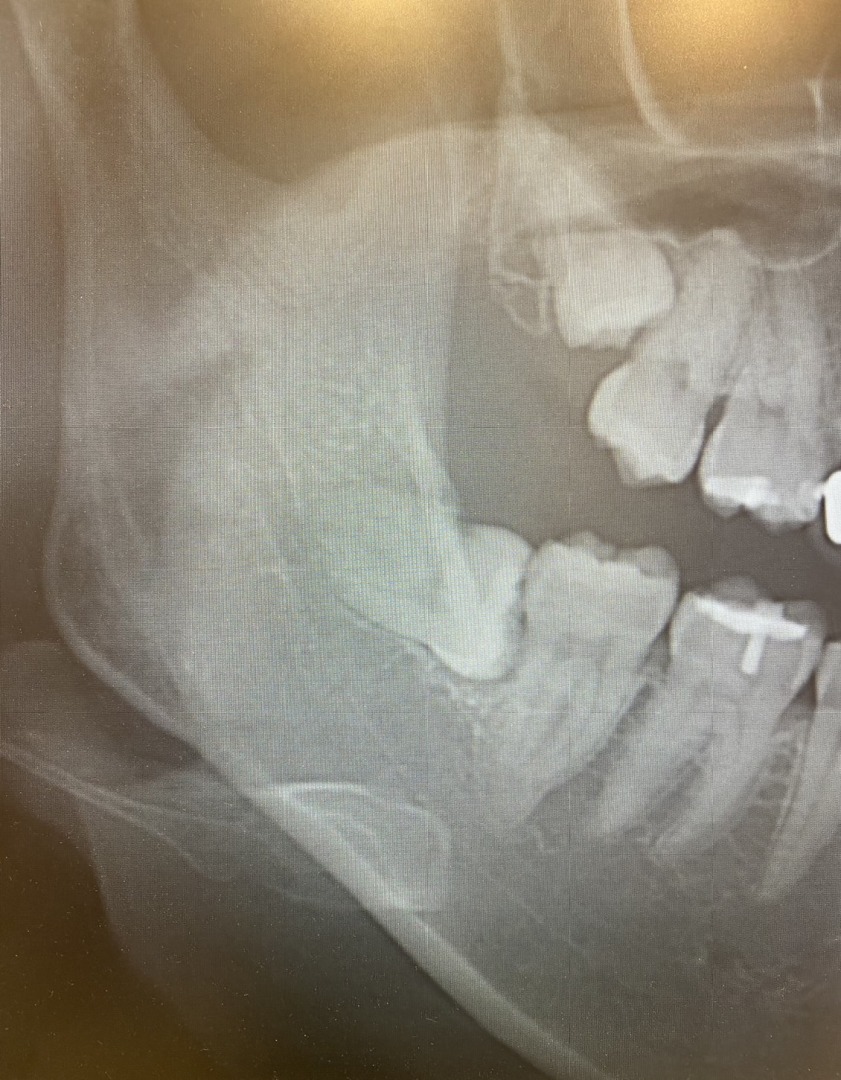

宮園歯科医院では、下顎の親知らずの抜歯(半埋伏抜歯、完全埋伏歯を含む)も行っております。

一般の歯科医院では大学病院に紹介となるようなケースも受け入れております。

半埋伏抜歯、完全埋伏歯は院長がしっかり時間をとって行います。

所要時間は30分程度となります。